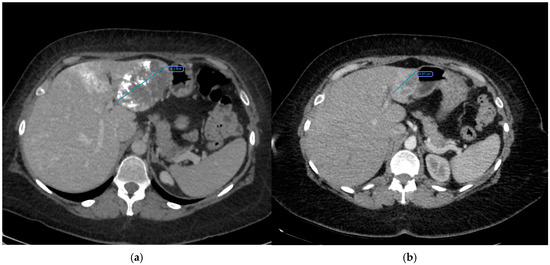

3. Results

| x, median (IQR) | 31 | 8.70 (7.50;10.55) |

| Volume before procedure, cm3, median (IQR) | 31 | 241.04 (123.98;539.08) |

| Volume regression, %, mean ± SD | 31 | 72.26 ± 19.01 |